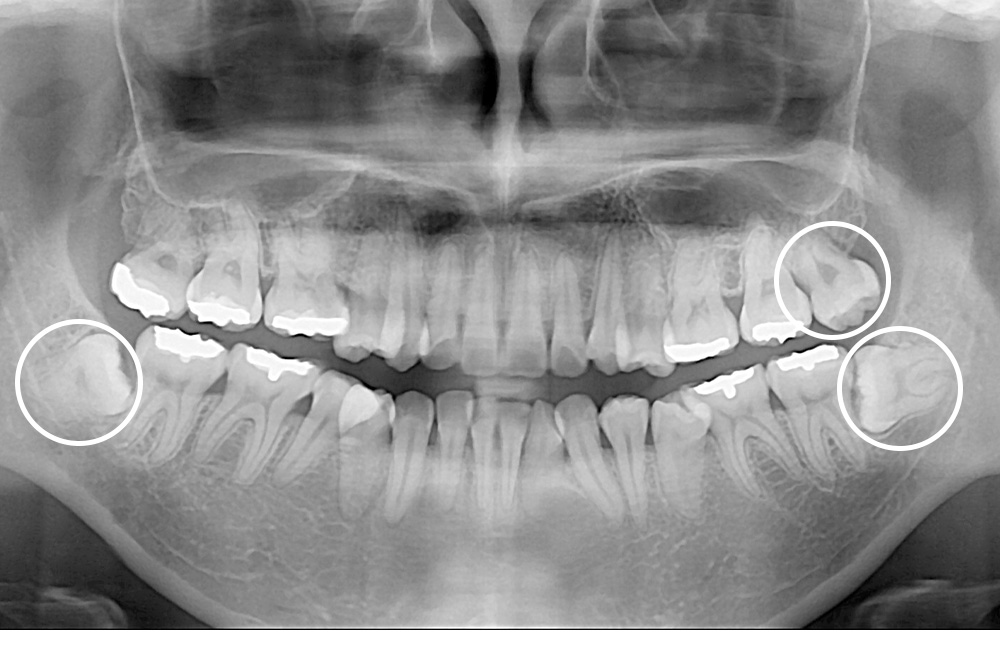

[사랑니] 매복 사랑니 발치

치료후 : 2018-05-10

세종치과는 구강악안면외과학 박사이신 원장님이 발치하는 치과입니다.